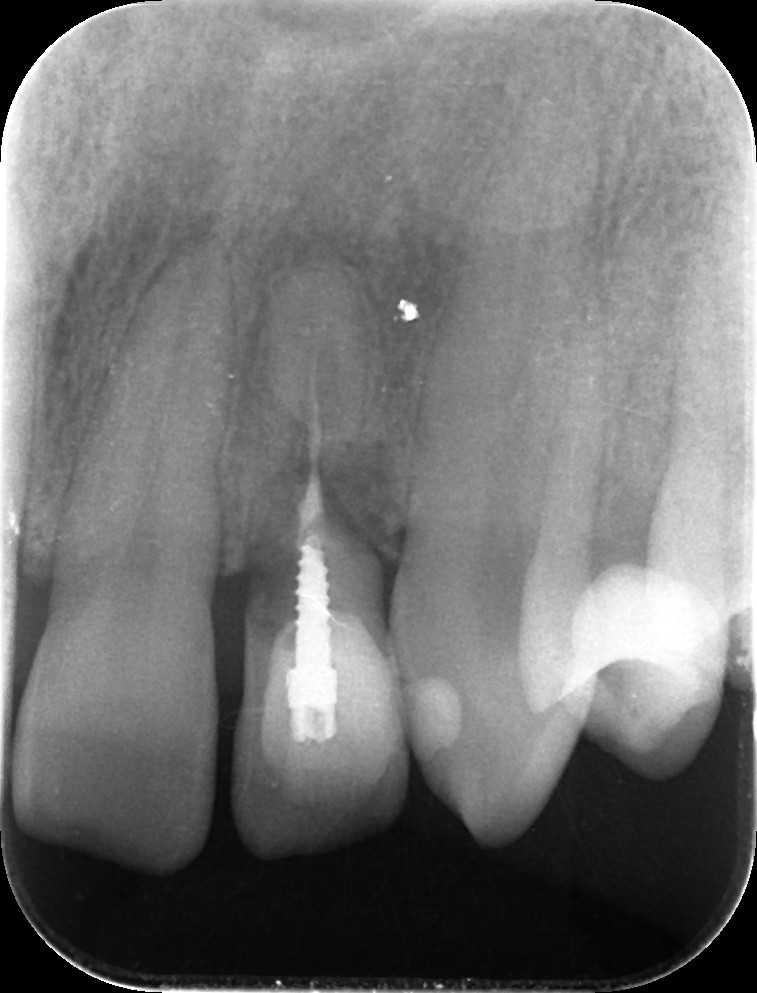

患者様は前歯の破折で来院されました。

しかし今回のように審美性や即時性が求められるケースでは、**抜歯と同時にインプラントを埋入する『抜歯即時インプラント』**が有効です。

さらに今回は、抜去した歯をトリミングして仮歯として即時に装着する方法を選択しました。

* 破折した前歯を抜歯

* 抜歯窩へ即時にインプラント埋入

* 抜去歯を加工し仮歯として装着